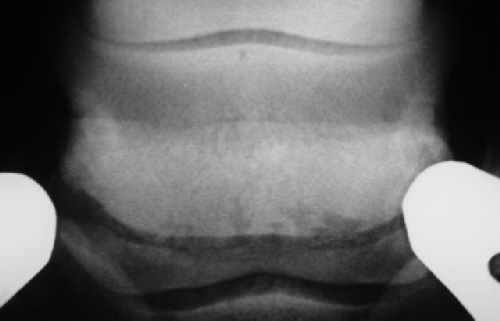

Hufrolle000802

Bei diesem Beispiel liegt in der Mitte ein verzweigter Kanal vor. Die Anzahl ist relativ hoch und die Kanäle liegen auch an den Seiten des Strahlbeines, was zur Einstufung Kategorie III bis IV bzw. Grad 3 führt.